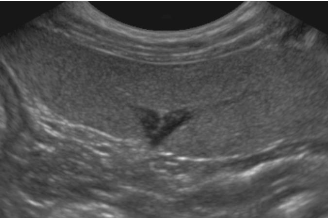

4 - Est ce que l’image obtenue vous semble correcte ?

A - Oui

B - Non

C - Je ne sais pas

5- Si non, expliquez quel réglage serait intéressant de modifier pour obtenir une image échographique correcte

A - J'ai coché oui à la réponse précédente

B - Diminuer la profondeur

C - Augmenter la profondeur

D - Augmenter le gain étagé en profondeur

E - Diminuer le gain étagé en profondeur

Question 4 : Réponse B

Question 5 : Réponse B